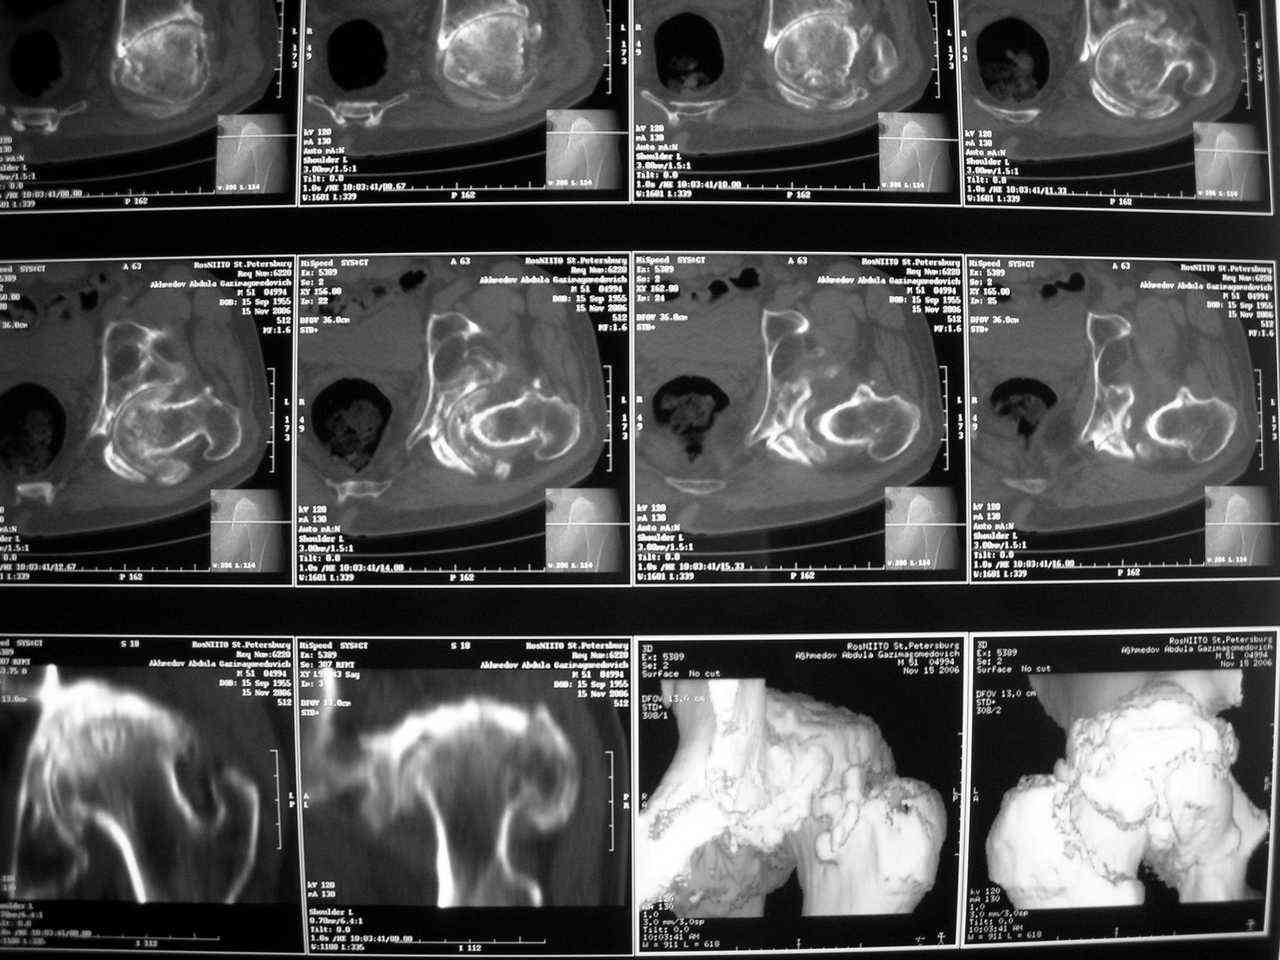

Еще одно наблюдение, неправильно сросшийся перелом заднего отдела ВВ с ввихом головки бедра 16-и летней давности.

С уважением, Р.Тихилов

Большое спасибо за ответ, примеры впечатляют, особенно случай с переломом задней колонны. Интересно отличаются ли у Вас доступ при значительных проблемах в задних отделах от стандартного, всегда ли хватает головки или берете кость из других мест, отличается ли послеоперационное ведение у таких больных (когда нагрузка?).